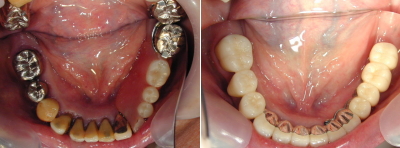

治療例を下記写真に示します。上あごは総入れ歯で下の部分入れ歯は非常に収まりの悪いものでした。左下奥歯の保存が難しいため抜歯をし、残っている歯も古い冠を撤去し土台から再治療させていただきました。歯周病が中等度の進行状況でしたので将来のリスク管理を考え固定式のブリッジではなく取り外しのできる タイプの入れ歯で対応しました。しかし左下奥歯が一本もないのでかみ合わせの力配分を考慮(右側だけの片咀嚼を避けるため)し、左下奥にインプラントを植立 (左側 上から4番目の写真です)し、右側の歯の負担を減らした設計としました。

写真は左側が「治療前」、右側が「治療後」です。